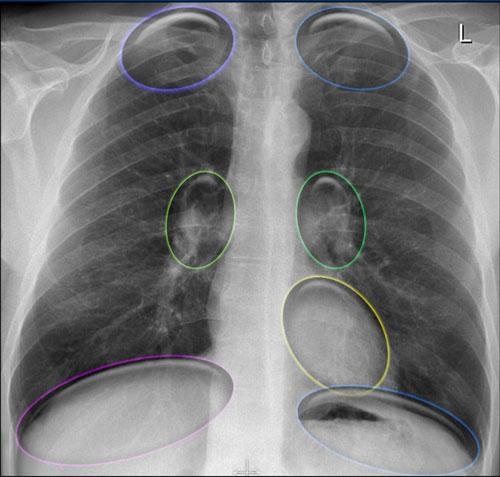

Các Vùng Khuất trên X-quang Ngực

Một số vùng nhất định của lồng ngực dễ bị bỏ sót trên phim X-quang ngực thường quy do sự chồng lấp của các cấu trúc giải phẫu. Các vùng này được gọi là “vùng khuất”, và cần được chú ý đặc biệt trong quá trình đọc phim để tránh bỏ sót các tổn thương kín đáo hoặc có ý nghĩa lâm sàng quan trọng.

Các Vùng Khuất Chính:

- Vùng đỉnh phổi

- Vùng rốn phổi

- Vùng sau tim

- Vùng dưới hoành (bên dưới các vòm hoành)

Vùng Khuất (1)

Điều quan trọng cần nhận biết là một thể tích đáng kể của nhu mô phổi kéo dài xuống bên dưới vòm hoành, đặc biệt ở các phân thùy đáy sau của thùy dưới.

Vùng này (minh họa bằng màu xanh dương) cần được đánh giá cẩn thận.